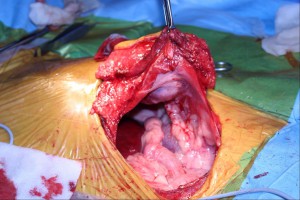

術中の写真

画像上が頭側、腹横筋・腹膜を切開し腹腔内から腫瘍を横隔膜越しに見ている像

画面左が頭側、腹腔内に突出した腫瘍の半分を切除しにかかっているところ